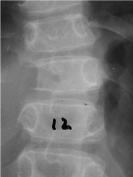

An 11-year-old boy previously fit and well presented with back pain and spinal deformation. There was a history of trauma and symptoms settled 2 months after. On examination, movements were restricted in flexion and extension (Figure 1). Plain radiographs (Figure 2) showed a lytic defect involving T11 vertebral pedicle. Tomographic images revealed a pathological T11 vertebra with several abnormalities in the posterior elements secondary to an expansile lesion.

Figure 2. Plain radiograph showing a lytic defect involving T11 vertebral pedicle.